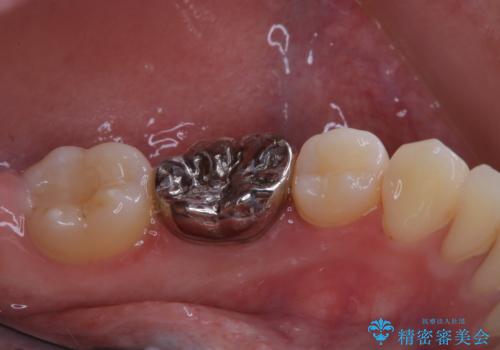

- 今後治療を進めていく予定で、まずはきれいにクリーニンングから行いたいとのことでした。PMTC60分コースを行いました。

PMTCを行う際には担当の歯科衛生士が、患者様1人1人の虫歯・歯周病などのリスク・ブラッシングスキルなどを確認します。

日々の磨き残しや唾液の成分などによりバイオフィルムや歯石はどうしても付着してしまいます。歯石や汚れを放置していると、そこで病原菌が繁殖す始めます。歯肉に炎症が生じると歯周病などの引き金となります。